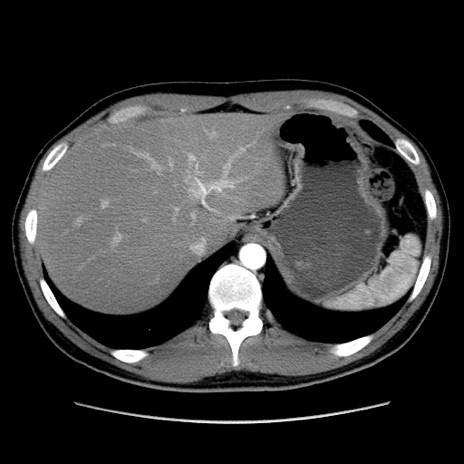

症例36(横断像)

【症例】20歳代 男性

【主訴】心窩部痛

【現病歴】今朝より上腹部痛あり。一旦軽快していたが再度出現したため救急要請。昨日夕に白身の魚を含む刺身を食べた。

【身体所見】BP 136/89mmHg、HR 74/min、BT 37.0℃、腹部:膨満、軟、心窩部に圧痛あり。反跳痛なし、筋性防御なし、腸雑音やや亢進あり。

【データ】WBC 17700、CRP 0.48